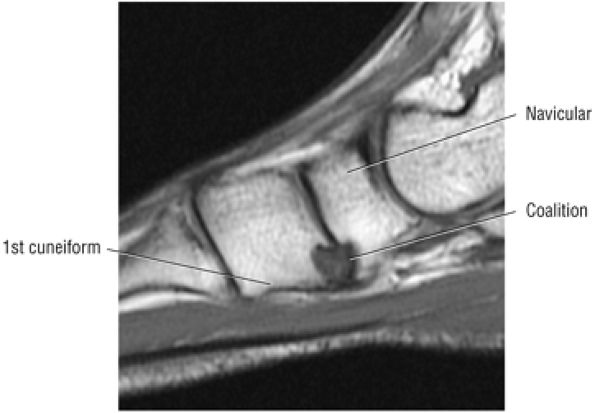

The spring ligament complex consists of three components: the lateral, intermediate, and superomedial oblique calcaneonavicular ligaments.

-

structures are critical static stabilizers of the medial longitudinal arch of the foot, providing support for the head of the talus at the talocalcaneonavicular joint (or acetabulum pedis). The other major stabilizer of the medial longitudinal arch, the PTT, is a dynamic stabilizer. Pathology of the spring ligament complex rarely occurs in isolation and is almost always associated with PTT dysfunction. Attention to the components of the spring ligament on routine MR imaging of the foot is important, since there is often a cascade of failures that can lead to or be seen with acquired pes planus deformity.